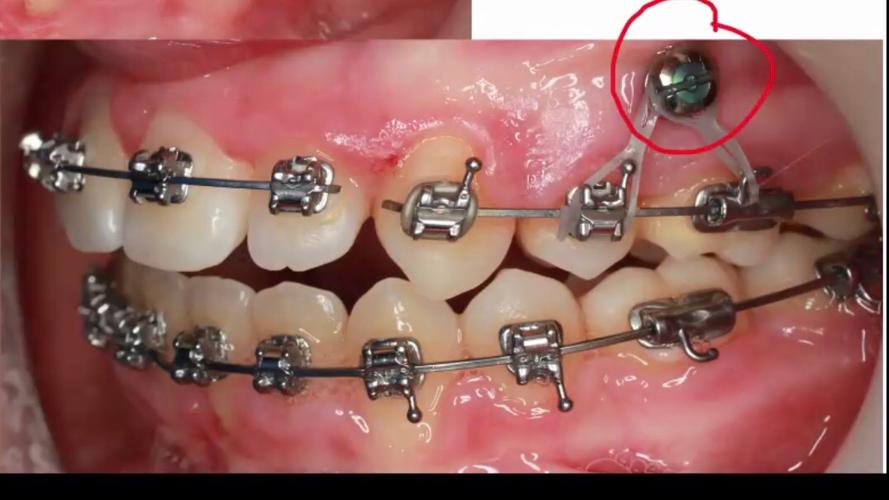

- 导向与植入:将支抗钉植入器尖端对准标记点,保持手机与牙面垂直(或根据骨面角度调整),低速(800-1200rpm)旋转植入,强调“手感反馈”——遇阻力时停止,避免强行穿透骨皮质,植入深度以钉头略低于牙槽骨平面为宜,便于后续正畸加力。

- 固定与检查:植入后用探针检查钉头稳定性,避免松动;若术中出血,可压迫止血或使用止血凝胶。

| 深度控制 | 钉头低于牙槽骨平面1-2mm,确保正畸加力时不压迫牙龈 | 过深可能导致植入困难,过浅易引发黏膜刺激 |

| 稳定性检查 | 植入后用镊子轻轻旋转钉头,确认无松动 | 若即刻松动,需调整位置或重新选择植入区 |